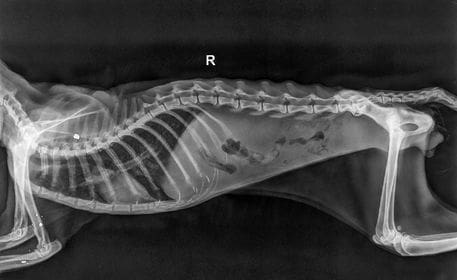

Vlasnik jedne mace pretrpio je strašnu patnju. Svog ljubimca je morao uspavati jer je netko mačku propucao lovačkom puškom. Pri tome je mačka zadobila prijelome noge i kralježnice te su je nažalost, morali uspavati.

Mještani su mačku našli u travi te joj nije bilo spasa.